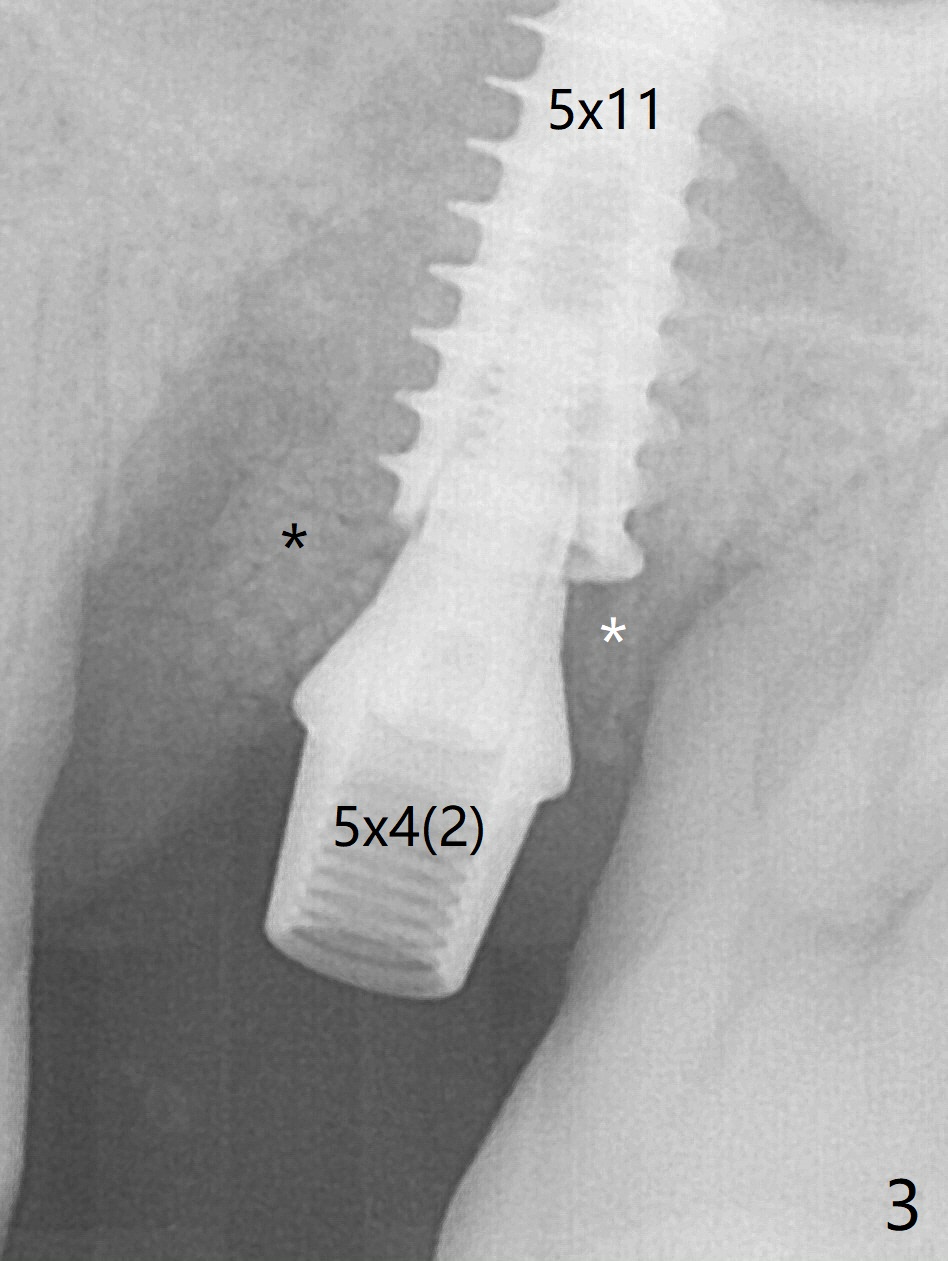

Osteotomy is initiated with Magic Split and 3 mm Magic Expander (ME, flapless) nearly 3 months post socket preservation. To improve the trajectory, the ME is redirected (Fig.1 red line). After use of 3.8 mm ME, Vanilla Graft is placed in the buccal and mesial aspects of the osteotomy. Following reuse of 3 and 3.8 mm MEs, a 4x11 mm dummy implant is inserted with stability (Fig.2 (*: allograft)). More of allograft is placed prior to placement of 5x11 mm IBS implant (Fig.3,4 (~30 Ncm)). The latter is placed palatal. Last the allograft is placed palatal. A 5x4(2) mm abutment is placed to hold periodontal dressing in place. When the ridge is narrow, the implant should be small; 4 mm probably the most appropriate in this case. There is a buccal gap 2 weeks postop (i.e., after dislodgement of periodontal dressing, Fig.5). The implant and abutment appear to be loose ~ 1.5 months postop. The pair abutment is changed to a healing one (5x3mm). The implant seems to be osteotointegrated 3.5 months posotp (Fig.6). Because of the mesial shift of the tooth #15 (Fig.6 arrow (6 months post #14 extraction; anterior open bite)), an angled abutment (5x4mm, 15 degree) is used (Fig.7). Limited orthodontic treatment has to be initiated because the mesially shifted #15 has no occlusal contact mesially (Fig.7 *). A provisional is fabricated with light supra-occlusion. A separator is placed between #14 and 15. Once a space is created in a week, acrylic is added to the distal surface of the provisional and the separator is re-used. In fact the implant is found to be unstable 4.5 months postop (Fig.8,9). The palatal (P) plate is thin and incomplete. The provisional is reduced infraocclusal. Two months the implant remains unstable and is removed.